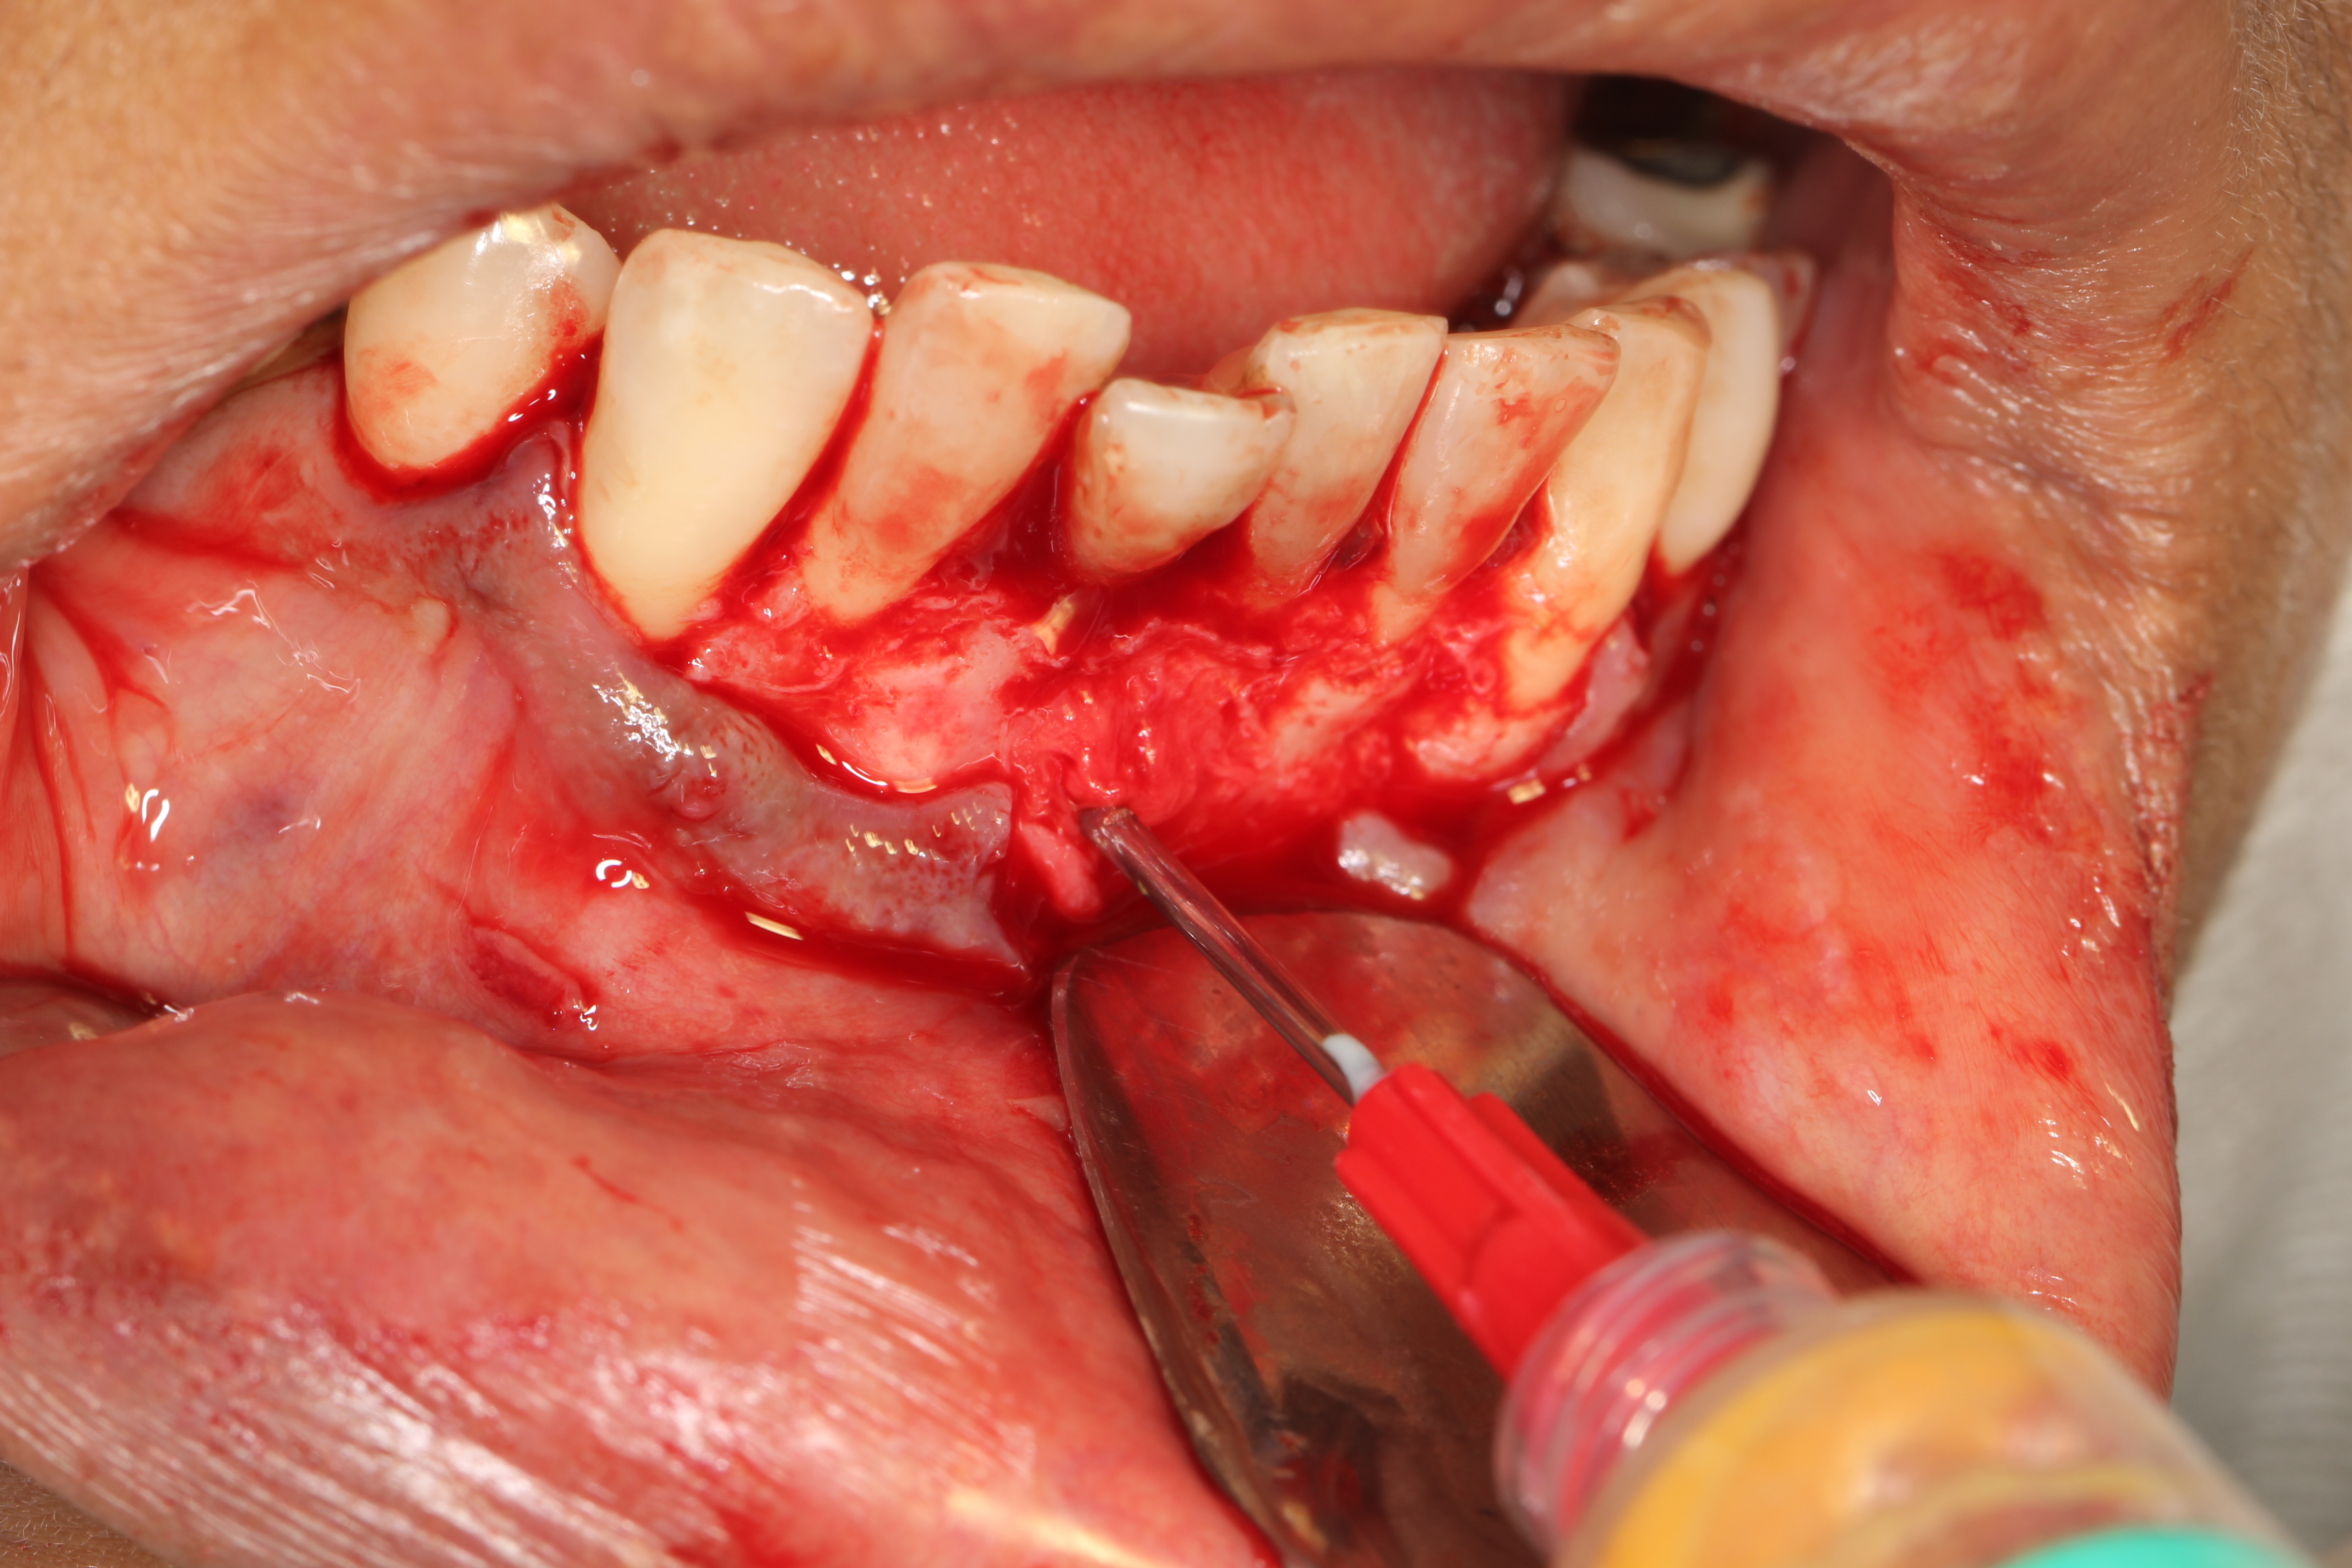

O objetivo deste estudo foi descrever uma técnica de tratamento conservadora, cuja conduta preconizada foi a realização da descompressão seguida pela enucleação cística através do relato de um caso de cisto periapical de grande extensão. Paciente de 50 anos de idade, melanoderma, apresentando cisto periapical com aproximadamente 4,5 cm em seu maior diâmetro associado ao incisivo central inferior esquerdo. Na primeira etapa do tratamento foi realizada descompressão cística e biopsia incisional, cujo exame histopatológico confirmou o diagnóstico clínico. Após 25 semanas de acompanhamento, houve uma considerável regressão do tamanho da lesão e a mesma foi enucleada sem comprometimento dos elementos dentários envolvidos e dos tecidos adjacentes. O relato de caso evidenciou que o tratamento cirúrgico e conservador pode ser um recurso em cistos periapicais de maior dimensão, sendo importante a cooperação do paciente no acompanhamento pós-operatório.